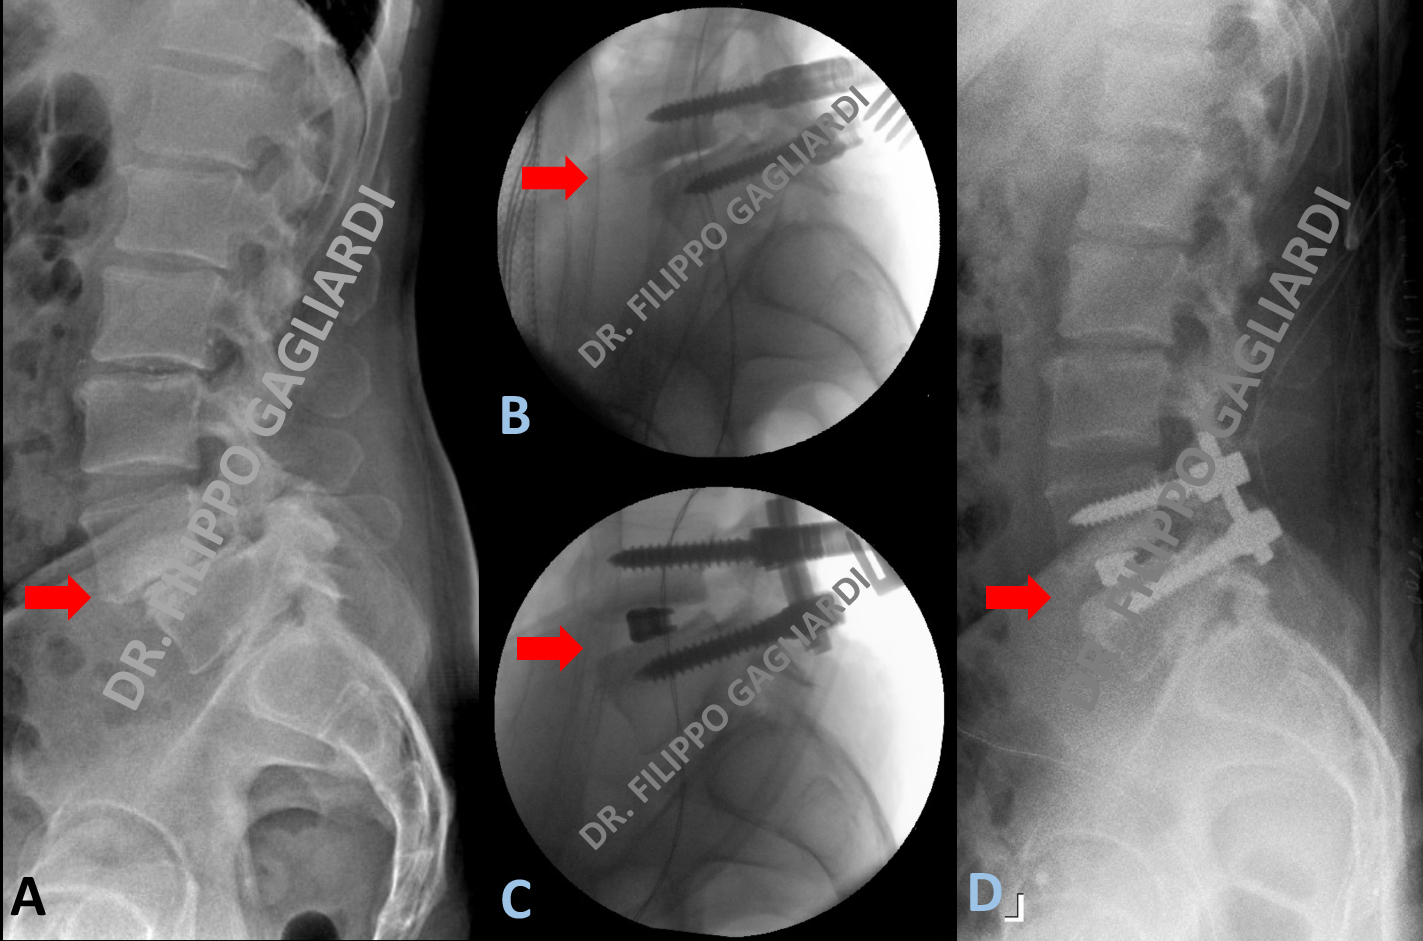

TLIF per spondilolistesi lombare

Caso di spondilolistesi malformativa (scivolamento in avanti della quarta vertebra lombare sulla quinta) (freccia rossa Figura A) in un uomo giovane con inteso dolore lombare. Il Paziente è stato sottoposto ad intervento di stabilizzazione lombare per via posteriore con posizionamento di una cage (gabbietta in titanio) al posto del disco intervertebrale mediante tecnica TLIF (trans-foraminal lumbar interbody fusion) (frecce rosse Figure B e C). Grazie all’utilizzo di viti da riduzione è stato possibile correggere la deformità riposizionando la vertebra nella sua normale sede anatomica come dimostrato del controllo post-operatorio (freccia rossa Figura D). La Figura A mostra lo studio RX pre-operatorio che documento lo scivolamento vertebrale. Le Figure B e C mostrano i controllo duranti l’intervento con posizionamento della cagee riduzione della listesi. La Figura D mostra il risultato post-operatorio con riallineamento del profilo vertebrale.